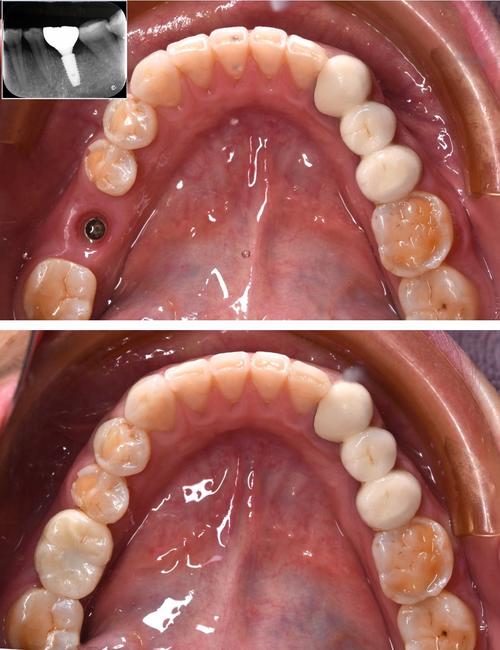

| 种植体植入 | 将经过表面处理的钛合金种植体植入拔牙窝,确保初期稳定性>35Ncm(必要时植骨)。 | 拔牙后立即 |

| 缝合与术后处理 | 无张力缝合牙龈,放置胶原蛋白海绵促进愈合;拍摄X线片确认种植体位置。 | 手术结束即刻 |

| 复查与修复 | 术后1周拆线;3-6个月复查骨结合情况;骨结合成功后取模,制作永久性牙冠并戴牙。 | 术后3-6个月 |